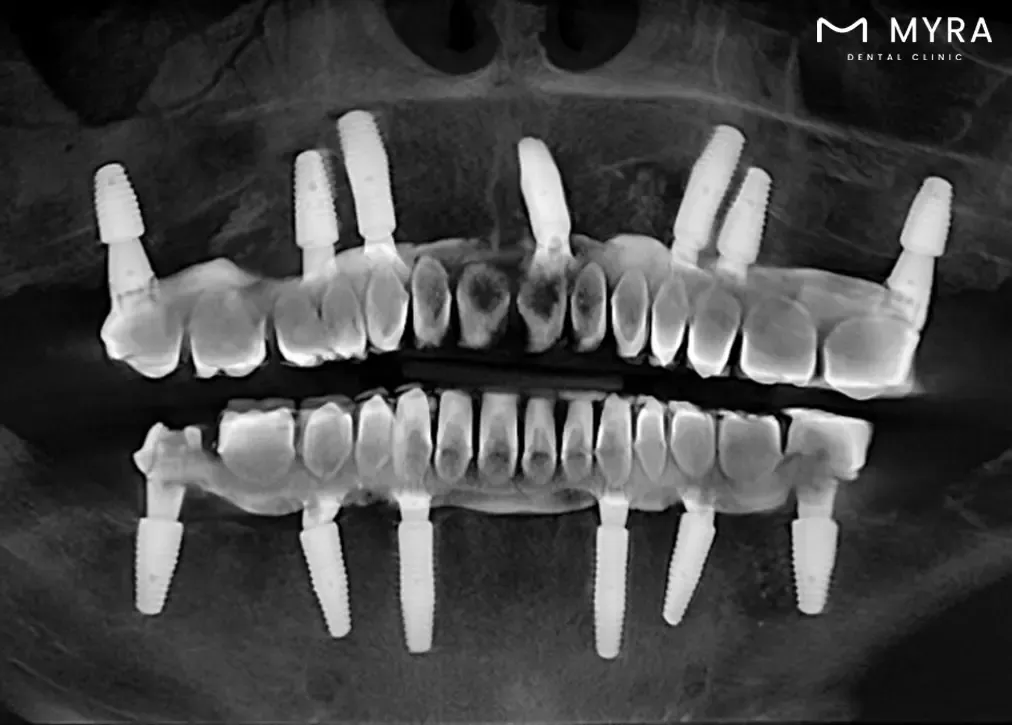

Implant Surgery Planning: Sirona 3D Dental Tomography is utilised to assess the bone structures of the jaw, allowing for precise planning of implant surgeries. The detailed images aid in determining the optimal placement of dental implants.

Detailed Imaging for Treatment Stages: The technology is frequently used in various treatment stages, including planning for implant surgery by advanced procedures, root canal treatment, and orthodontic interventions. The detailed imaging allows for precise assessments, contributing to successful outcomes in these procedures.

Efficient Planning for Implant Surgery: The technology is particularly useful in planning and guiding implant surgeries. It allows for a thorough evaluation of the jawbone structure, facilitating precise implant placement and increasing the likelihood of successful outcomes.

Sirona 3D Dental Tomography allows dentists to gain a more in-depth understanding of dental and jaw-related issues. The three-dimensional images enable precise and accurate diagnoses of conditions such as tooth decay, buried or impacted teeth, fractures resulting from trauma, bone defects, and the periodic assessment of implants.

The procedure aids in treatment planning by offering a higher level of detail and accuracy. Dentists configure root canals, measure root canal dimensions, and conduct detailed assessments of bone density, sinuses, and joints. The technology helps in the planning of dental implant procedures, offering a three-dimensional evaluation of the jawbone structure.

Imaging before Implant treatment is very important. Because the 3D tomography X ray shows the condition of the jawbone very clearly, they contribute to proper planning before surgery. Bone density is a measure of bone density. Thus, it is determined which surgical techniques will be used and exactly what can be done before the procedure begins. After surgery, CT scans can be taken to control implant placement and bone support.